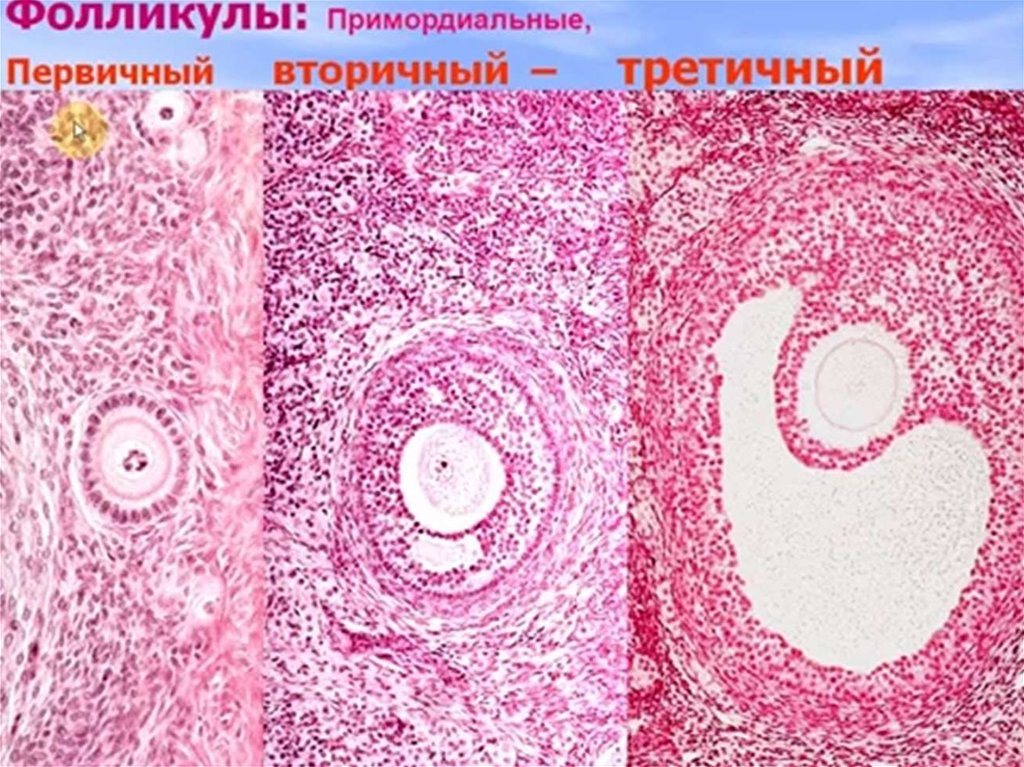

Созревание фолликула в яичнике: этапы и процессы